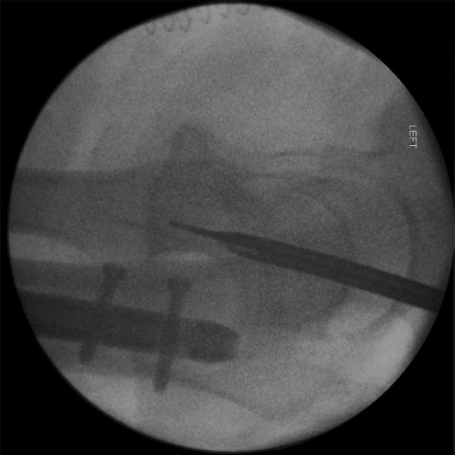

什么是c型臂术中透视骨科精读 | 股骨近端骨折的转子区域与矢状面力线术中透视技巧_https://www.jmylbn.com_新闻资讯_第7张

图7

轴侧位:使股骨干、股骨颈和股骨头呈共线对齐,让术者能够观察到矢状面的细微复位不良。此外,植入物在股骨颈和股骨头内的放置情况可清晰显影。此体位最适用于将植入物定位到股骨头内,但股骨距区域显示不佳。应与标准侧位成像结合使用。